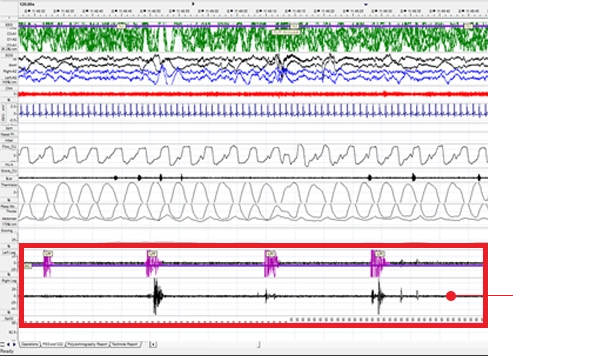

주기성사지운동증 환자의 수면그래프

다리근육에 붙인 근전도 센서로 다리 움직임을 관찰,

다리 증상으로 뇌의 각성이 나타난 것을 확인할 수 있음.

* 개인마다 차이가 있을 수 있습니다.

※ 코슬립에서 치료받은 환자의 실제 수면그래프입니다.